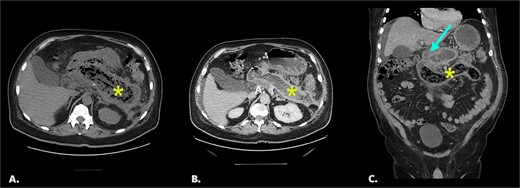

Final CT shows dilated fluid-filled small bowel loops with interval migration of the bezoar into the distal small bowel (Fig. 2).

Follow-up CT with IV contrast (portal venous phase). Fig. 2A: an axial image shows a collapsed pancreatic bed (↞) containing trace fluid, dilated small bowel loops (←), and perihepatic free fluid. Fig. 2B: coronal image of same study shows interval migration of the bezoar into the distal small bowel (*) and upstream dilated, fluid-filled small bowel (←).